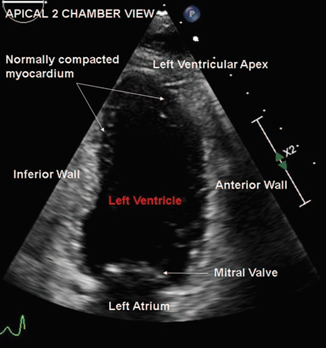

In the early intrauterine period, the myocardium exists as a loose meshwork. By the 18th week of life, coronary vasculature is established and the loose myocardial meshwork compacts. This process is responsible for the relatively smooth appearance of the normal left ventricular wall (Fig. 2). The embryogenic hypothesis suggests that arrest of this process causes ILVNC (see Video, Supplemental Digital Content, http://links.lww.com/RCA/A852). The non embryogenic hypothesis proposes that chronic changes in left ventricular loading conditions leads to hypertrabeculation.1,2

Figure 2 Apical 2 chamber view displaying scarcely trabeculated normal left ventricular myocardial walls.